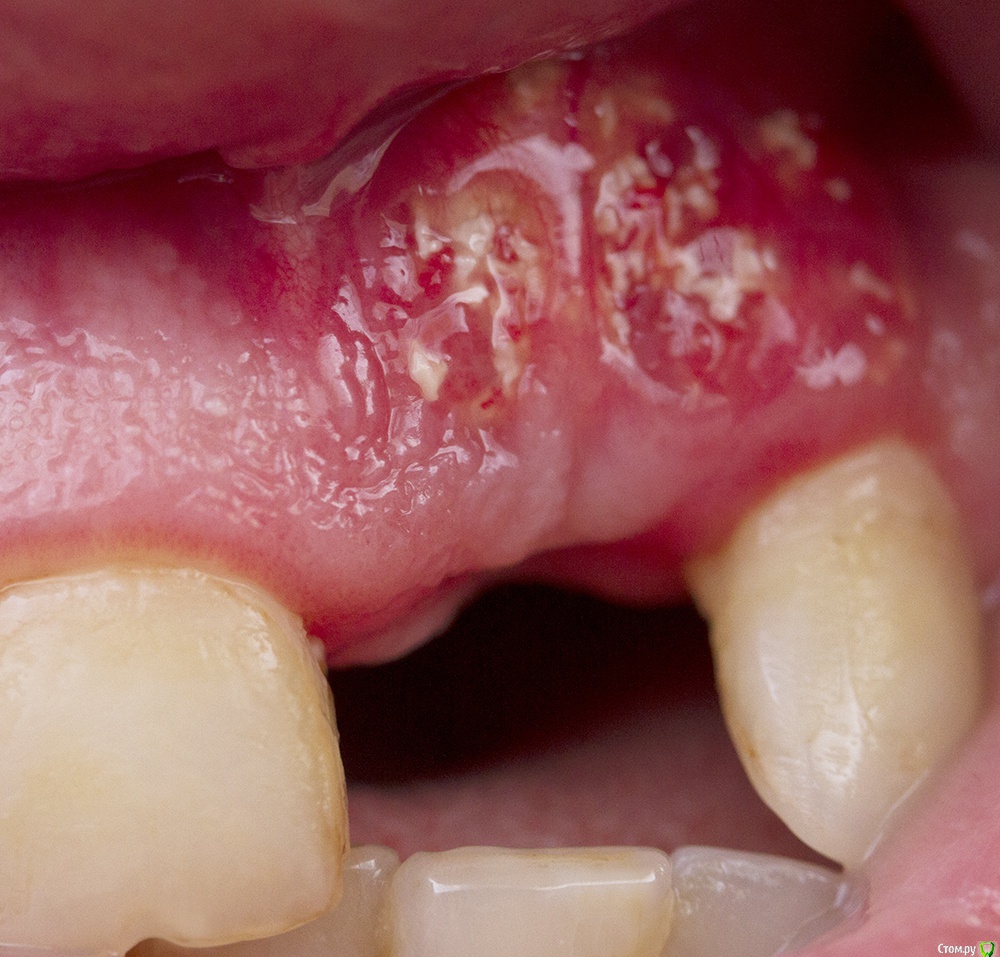

AnaY007 Опубликовано 28 января, 2015 Поделиться Опубликовано 28 января, 2015 Добрый день!Три с половиной месяца назад мне был удален верхний первый резец, зуб был сильно разрушен, в т.ч. была разрушена стенка лунки, одновременно сделана костная пластика - искусственный костный блок, мембрана и стружка ещеНа десне в зоне удаленного зуба все не проходит раздражение - покраснение, и на поверхности образуется белый налет, иногда как белые костные крошки, отека нет, боли нет. Это нормально или с приживлением кости проблемы и надо идти к врачу? Переживаю - в интернетах после остеопластики уже через пару недель-месяц розовая здоровая десна на фотографиях. Ссылка на комментарий

AnaY007 Опубликовано 29 января, 2015 Автор Поделиться Опубликовано 29 января, 2015 снимок во рту ( прикреплен) и ОПТГ перед пластикой https://picasaweb.google.com/116859165867195399731/20140903?authkey=Gv1sRgCML06f_pgc3BLA#6109712106199120002 Ссылка на комментарий

Большой Зеленый Опубликовано 30 января, 2015 Поделиться Опубликовано 30 января, 2015 Срочно к доктору. Скорее всего придется все вычищать. 3 Ссылка на комментарий

IvanK Опубликовано 30 января, 2015 Поделиться Опубликовано 30 января, 2015 Срочно к доктору. Скорее всего придется все вычищать. или частично Ссылка на комментарий